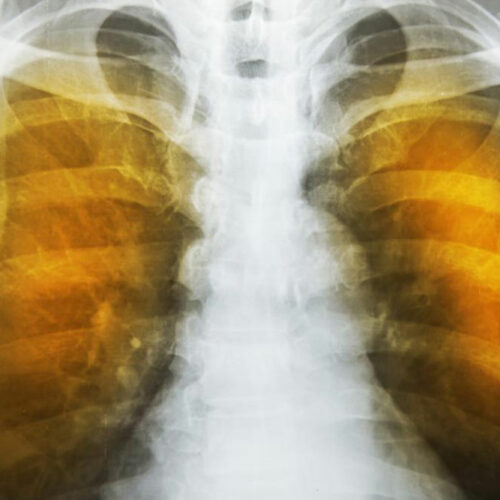

Emphysema is an oppressive respiratory disorder which results from the disintegration of the alveoli, i.e., the tissues where the interchange of gas with blood takes place. Destruction in any large scale will reduce the gas transfer area and the process of gas transfer itself, leading to oxygen starvation or hypoxia.